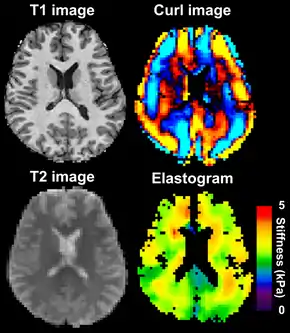

MRE is conducted in three steps: first, a mechanical vibrator is used on the surface of the patient's body to generate shear waves that travel into the patient's deeper tissues; second, an MRI acquisition sequence measures the propagation and velocity of the waves; and finally this information is processed by an inversion algorithm to quantitatively infer and map tissue stiffness in 3-D.[2][3] This stiffness map is called an elastogram, and is the final output of MRE, along with conventional 3-D MRI images as shown on the right.[2]

![]() Magnetic resonance elastography of the brain. A T1 weighted anatomical image is shown in the top-left, and the corresponding T2 weighted image from the MRE data is shown in the bottom-left. The wave image used to make the elastogram is shown in the top-right, and the resulting elastogram is in the bottom-right. | |

MRE of the brain [27] was first presented in the early 2000s.[28][29] Elastogram measures have been correlated with memory tasks,[30] fitness measures,[31] and progression of various neurodegenerative conditions.[27] For example, regional and global decreases in brain viscoelasticity have been observed in Alzheimer’s disease[32][33] and multiple sclerosis.[34][35] It has been found that as the brain ages, it loses its viscoelastic integrity due to degeneration of neurons and oligodendrocytes.[36][37] A recent study looked into both the isotropic and anisotropic stiffness in brain and found a correlation between the two and with age, particularly in gray matter.[38]